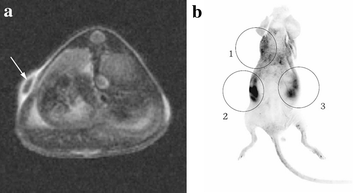

Breast cancer (BC) is a serious disease to threat lives of women. Numerous studies have proved that BC originates from cancer stem cells (CSCs). But at present, no one approach can quickly and simply identify breast cancer stem cells (BCSCs) in solid tumor. Nanotechnology is probably able to realize this goal. But in study process, scientists find it seems that nanomaterials with one modality, such as magnetic resonance imaging (MRI) or fluorescence imaging (FI), have their own advantages and drawbacks. They cannot meet practical requirements in clinic. The nanoprobe combined MRI with FI modality is a promising tool to accurately detect desired cells with low amount in tissue. In this work, we briefly describe the MRI and FI development history, analyze advantages and disadvantages of nanomaterials with single modality in cancer cell detection. Then the application development of nanomaterials with dual-modality in cancer field is discussed. Finally, the obstacles and prospective of dual-modal nanoparticles in detection field of BCSCs are also pointed out in order to speed up clinical applications of nanoprobes.